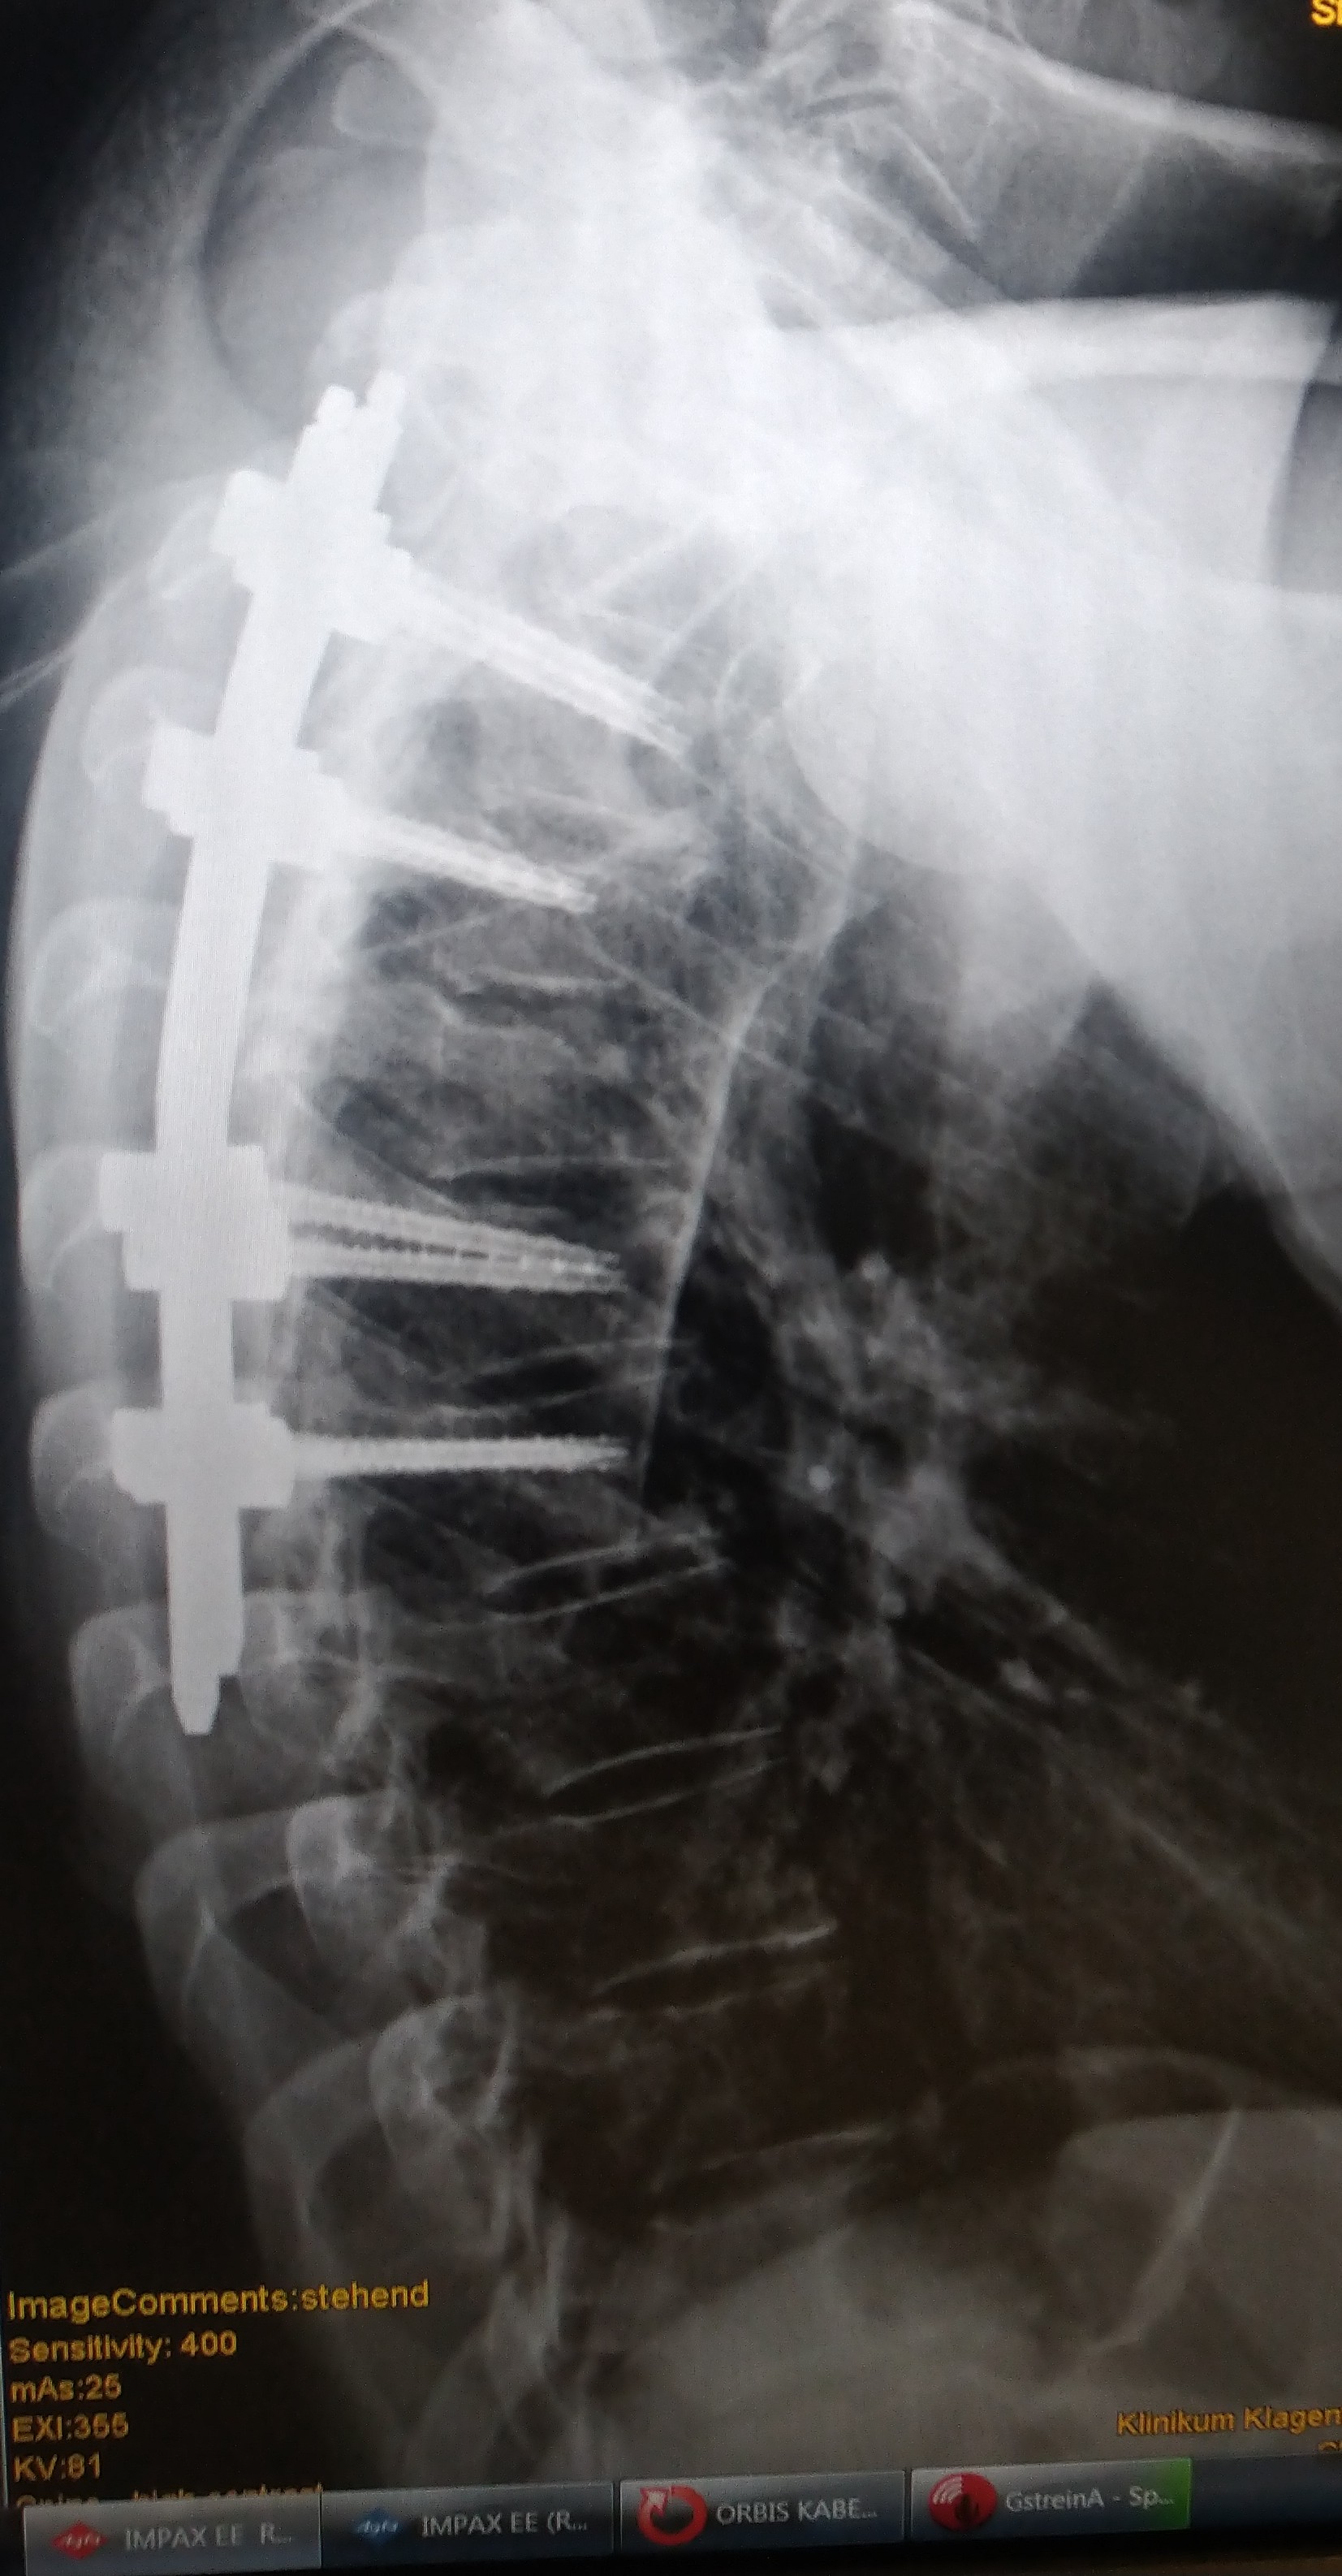

Es waren 2 Halswirbel gebrochen,

3 Brustewirbel und Brustbein..

Brustwirbel wurden eben weil das Brustbein gespalten war on t3-t7 verschraubt.. Kommt ach einem Jahr wieder raus.. Wirklich schlau is es warscheinlich nicht so zu fahren.. Ich weiss

Hals waren Bogenbrüche und Brustwirbel Stauchbrüche